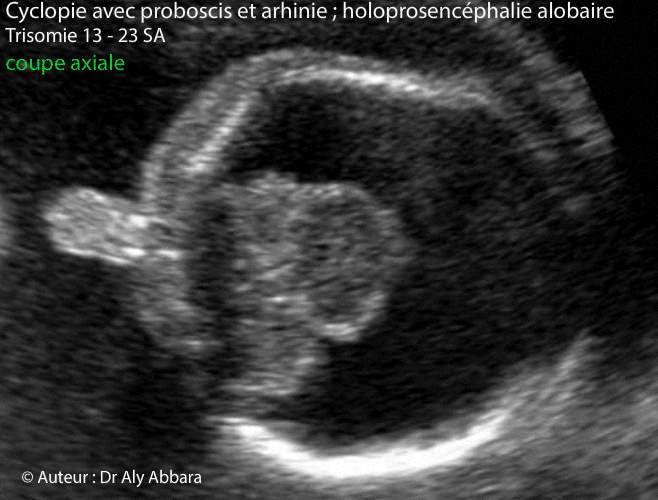

Cyclopie - Holoprosencéphalie - trisomie 13 - 23 SA

Images échographiques montrant deux coupes axiales du pôle céphalique d'un fœtus présentant un proboscis, arhinie et une holoprosencéphalie alobaire avec hydrocéphalie majeure ; une cyclopie caractérisée par la fusion deux yeux sur la ligne médiane pour former une seule masse oculaire (synophtalmie).

Dans le cas présenté dans cet article, le fœtus est trisomique 13 âgé de 23 SA.

L'étude de la morphologie révèle la présence d'autres anomalies en dehors de la séquence holoprosencéphalie alobaire avec microcéphalie (périmètre céphalique = 170 mm, soit "-3,24 DS") : une hypoplasie du pavillon de l'oreille externe ; un spina bifida aperta ; un spot blanc intracardiaque ; une hyperéchogénicité intestinale ; une artère ombilicale unique ; main crispée unilatérale et enfin, un retard de croissance in utero modéré et symétrique.